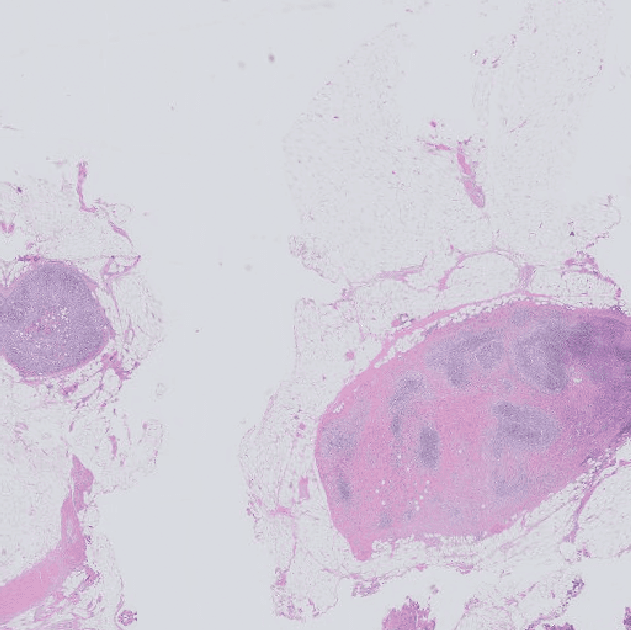

Abstract:Tumor proliferation is an important biomarker indicative of the prognosis of breast cancer patients. Assessment of tumor proliferation in a clinical setting is highly subjective and labor-intensive task. Previous efforts to automate tumor proliferation assessment by image analysis only focused on mitosis detection in predefined tumor regions. However, in a real-world scenario, automatic mitosis detection should be performed in whole-slide images (WSIs) and an automatic method should be able to produce a tumor proliferation score given a WSI as input. To address this, we organized the TUmor Proliferation Assessment Challenge 2016 (TUPAC16) on prediction of tumor proliferation scores from WSIs. The challenge dataset consisted of 500 training and 321 testing breast cancer histopathology WSIs. In order to ensure fair and independent evaluation, only the ground truth for the training dataset was provided to the challenge participants. The first task of the challenge was to predict mitotic scores, i.e., to reproduce the manual method of assessing tumor proliferation by a pathologist. The second task was to predict the gene expression based PAM50 proliferation scores from the WSI. The best performing automatic method for the first task achieved a quadratic-weighted Cohen's kappa score of $\kappa$ = 0.567, 95% CI [0.464, 0.671] between the predicted scores and the ground truth. For the second task, the predictions of the top method had a Spearman's correlation coefficient of r = 0.617, 95% CI [0.581 0.651] with the ground truth. This was the first study that investigated tumor proliferation assessment from WSIs. The achieved results are promising given the difficulty of the tasks and weakly-labelled nature of the ground truth. However, further research is needed to improve the practical utility of image analysis methods for this task.

Abstract:The progression of breast cancer can be quantified in lymph node whole-slide images (WSIs). We describe a novel method for effectively performing classification of whole-slide images and patient level breast cancer grading. Our method utilises a deep neural network. The method performs classification on small patches and uses model averaging for boosting. In the first step, region of interest patches are determined and cropped automatically by color thresholding and then classified by the deep neural network. The classification results are used to determine a slide level class and for further aggregation to predict a patient level grade. Fast processing speed of our method enables high throughput image analysis.